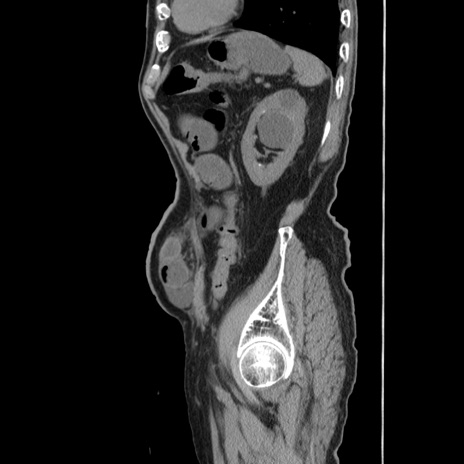

冠状断像

【症例】80歳代男性

【主訴】左側腹部痛、嘔吐

【現病歴】本日早朝より左腹部に痛みあり。昼頃嘔吐認めたため、救急要請。

【既往歴】直腸癌(Mile手術)、胆摘

【身体所見】意識清明、BT 35.9℃、BP 221/93mmHg、SpO2 97%(RA) 、腹部:左ストーマ周囲に限局性の腹部膨隆あり。 膨隆部自発痛・圧痛あり・軟。

【データ】WBC 7700、CRP 0.09